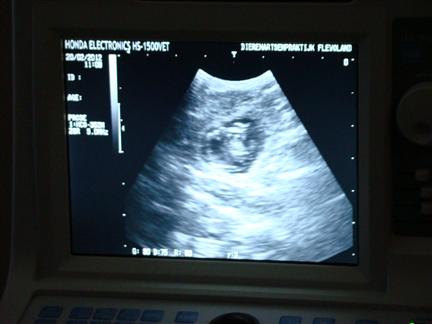

| FEEST, Fleur is drachtig, hier zie je één van de pupjes in wording |

in de donkere vlek (het vruchtwater) zie je een puppy |